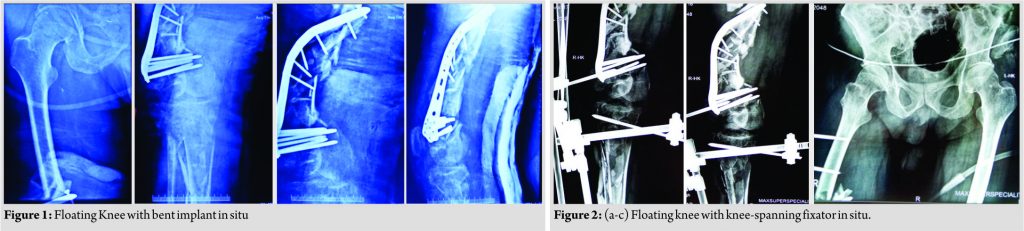

A 56-year-old diabetic, hypertensive man on antipsychotic medications who jumped from about 30 feet height, sustained polytrauma and was admitted in a local hospital. After initial resuscitation and advanced trauma life support (ATLS) care, he was intubated and put on ventilator support. He was diagnosed with bilateral hemothorax and his right lower limb X-rays showed fracture lower one-third femur with extensive metadiaphyseal comminution and fracture ipsilateral proximal tibia extending to metaphysis. A locking distal femoral locking plate was present and had bent (Fig. 1). As per records, he had 3*2 cm wound on anterior aspect of thigh which was thoroughly washed, debrided, and sutured and damage control [7]surgery was done in the form of knee-spanning fixator (Fig. 2) and the patient was put on intravenous antibiotics. He stayed in the intensive care unit (ICU) for 7 days, after which he was shifted to our center. As a part of repeat evaluation, all his necessary X-rays were retaken (Fig. 3) which revealed resolution happening in bilateral hemothorax. The right lower limb X-rays revealed knee-spanning external fixator with fracture of lower end femur and proximal end tibia with bent implant in situ (Fig. 2).